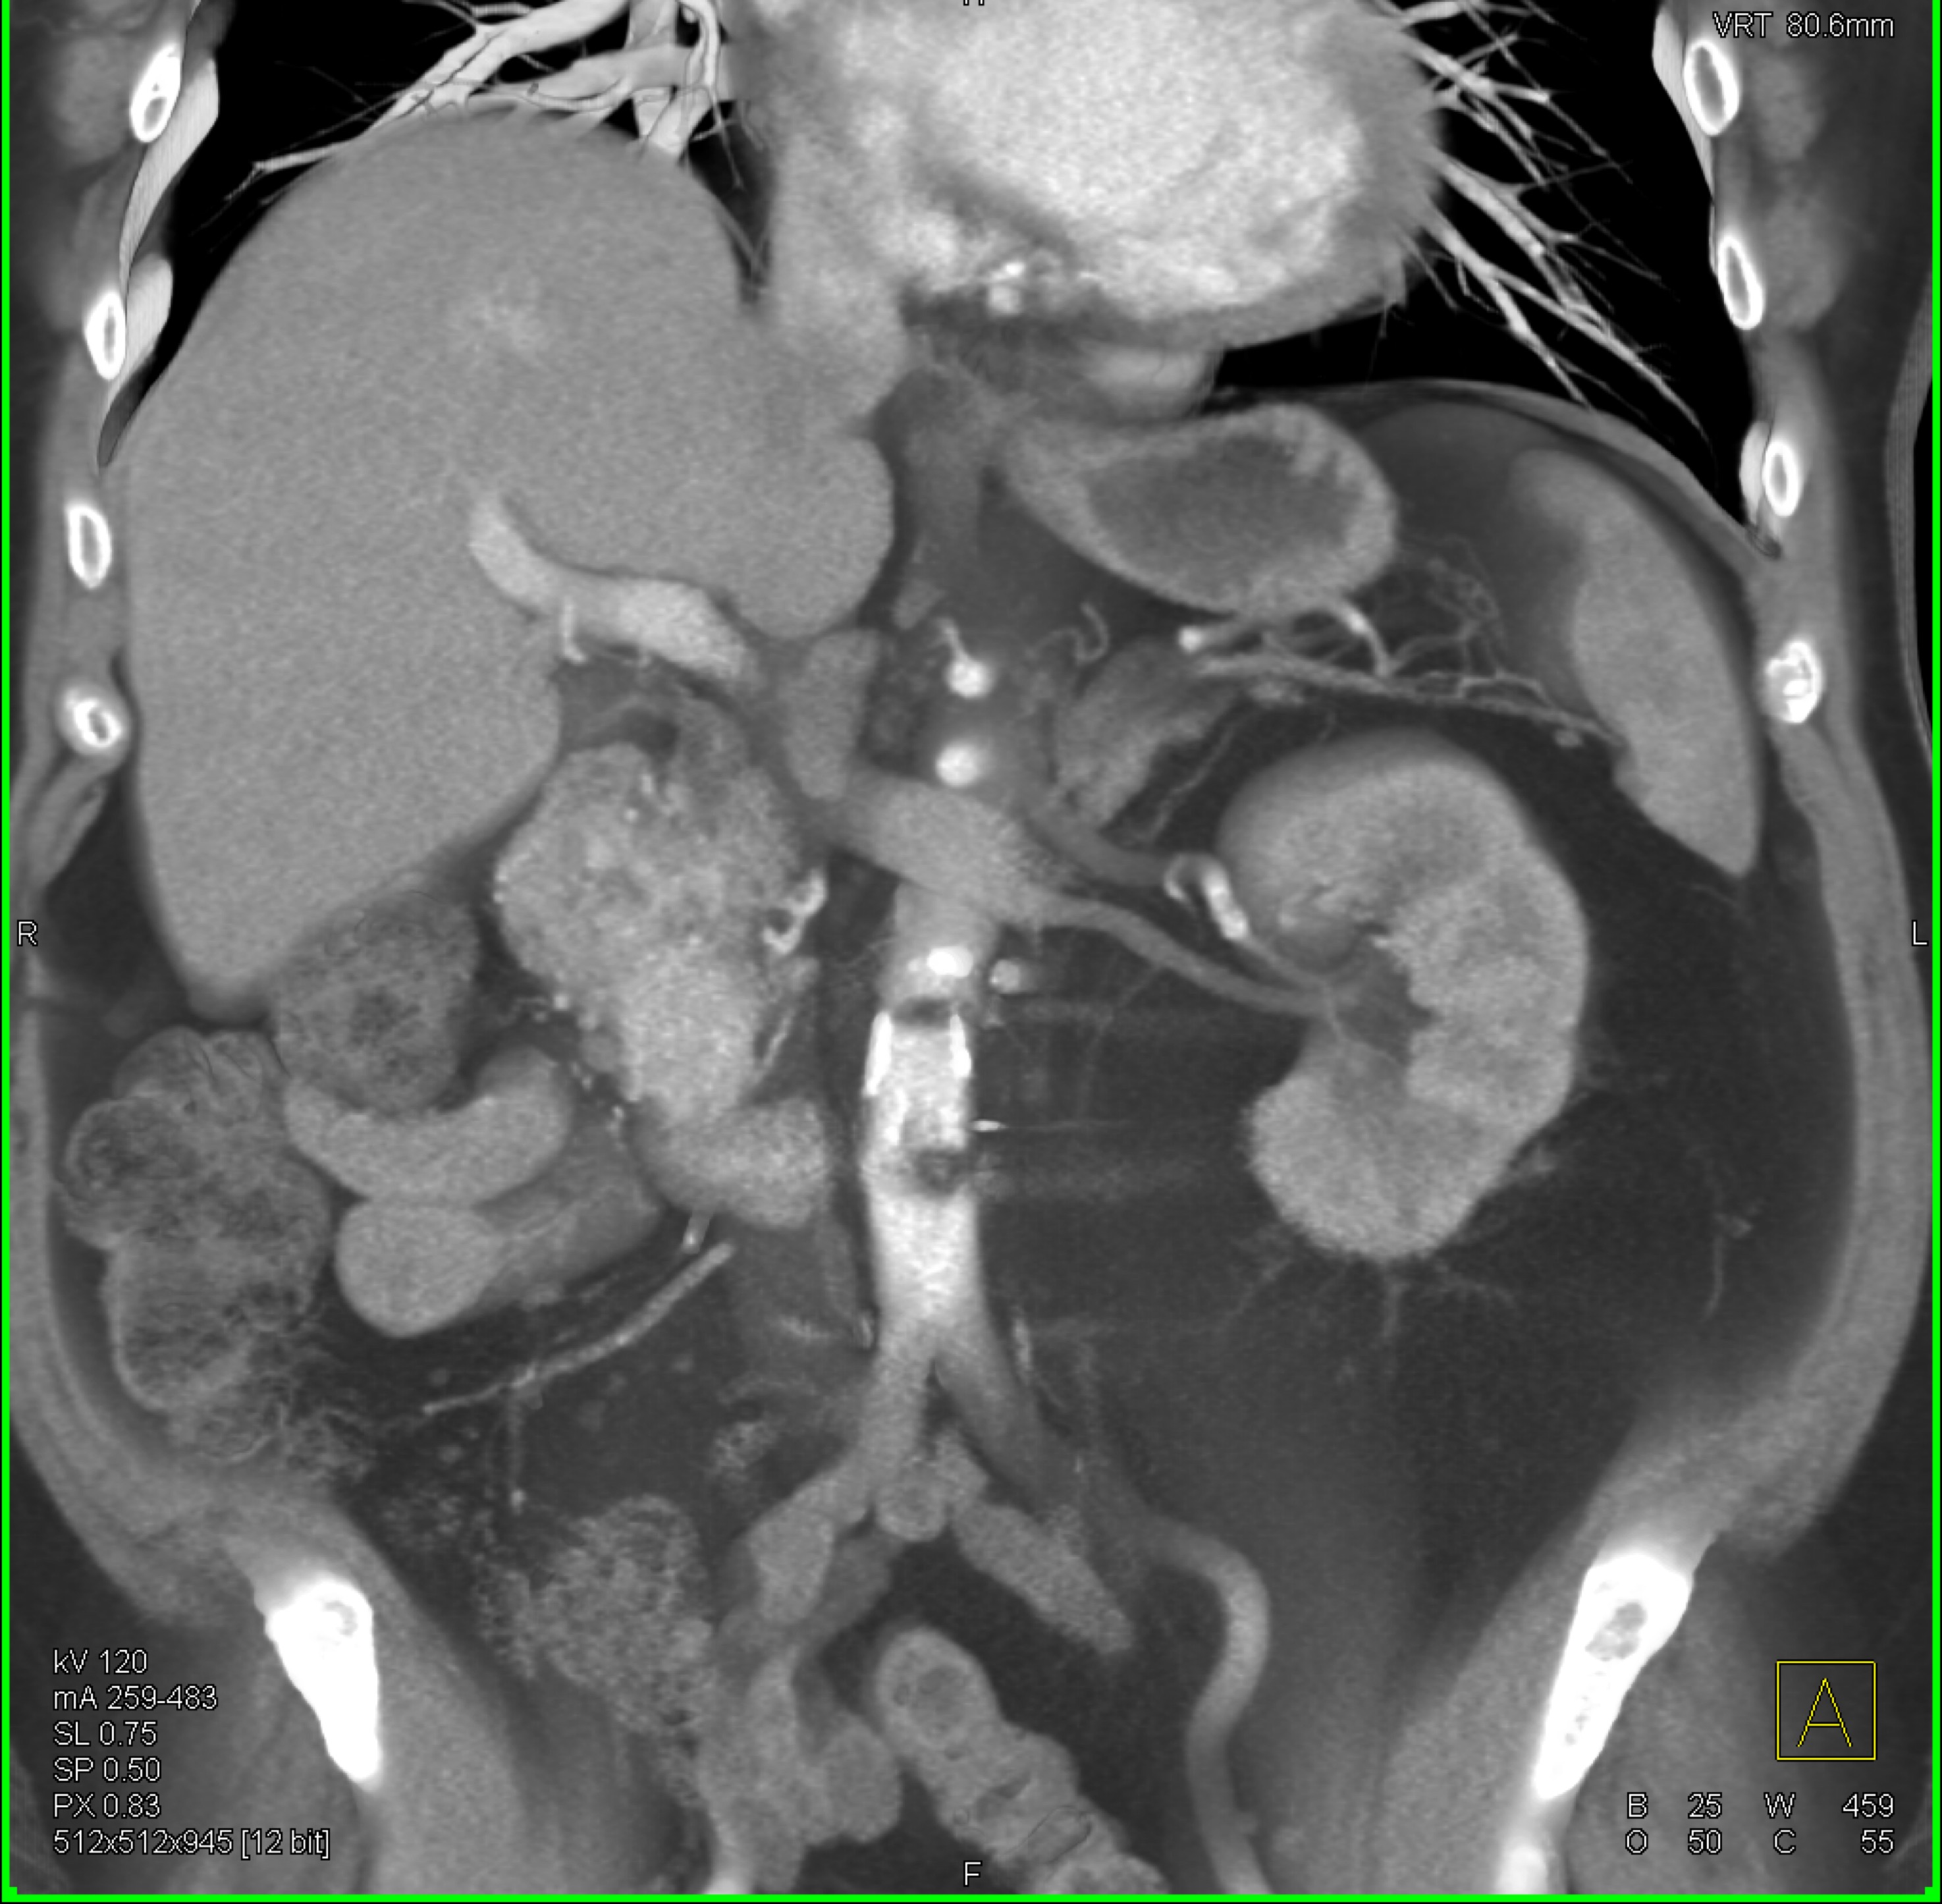

2) In this patient on dialysis for ESRD the best diagnosis is?

normal bypass graft

AV fistulae with aneurysms

vasculitis

infectious vascular disease